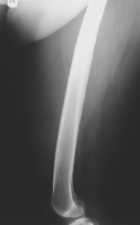

P.G. - 49 year old female presents with a two month hx of painful right thigh mass.

Zoom image: Radiological image Radiological image.